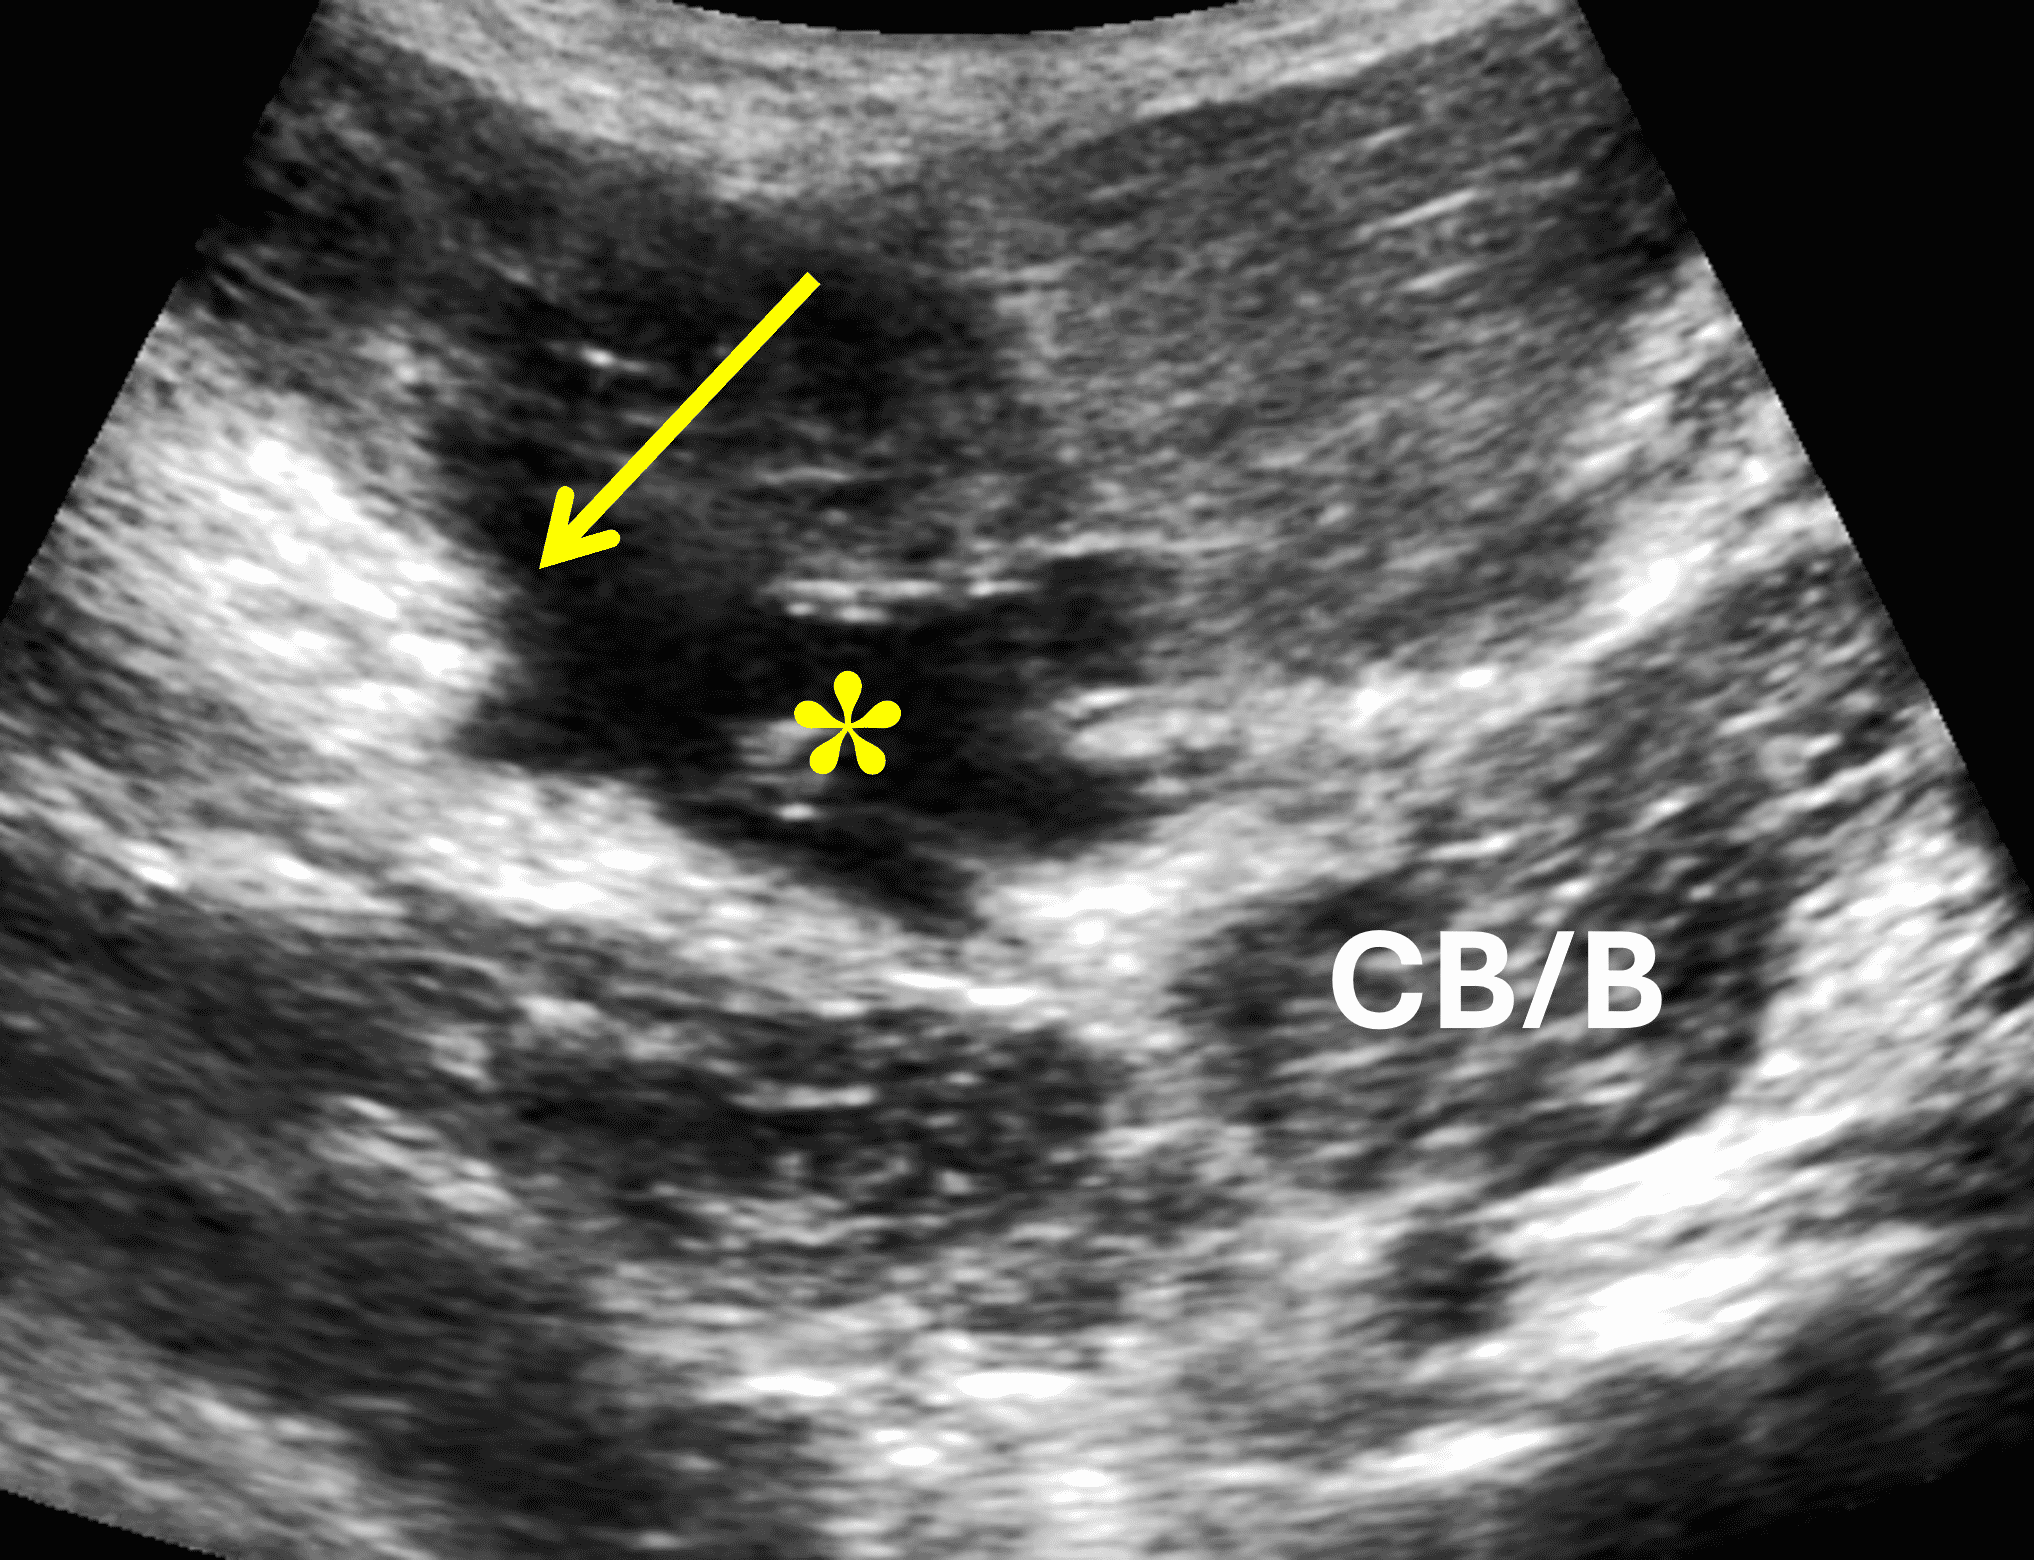

- Determine if tear is complete 2-layer or partial, 1-layer by looking at extent of edema into muscle fibers on coronal and sagittal sequences and analyzing visible torn and intact tendon leaflets (Figures 12, 13, and 14).

Figure 12: Partial-thickness, full-width (1-layer) tear of pectoralis major tendon at the humeral attachment. (12A) Axial T2-weighted image shows an intact tendon (anterior leaflet) inserting on the humerus (red arrows), approximately half the thickness of the normal tendon. The torn, retracted stump of the deep leaflet is visible (yellow arrow) medial to the hematoma. (12B and 12C) Transverse ultrasound images confirm the retracted torn deep tendon layer (yellow arrow) medial to the hematoma (asterisk), as well as the intact anterior tendon layer (red arrows). H = humerus, CB/B = coracobrachialis/short head biceps muscle bellies.